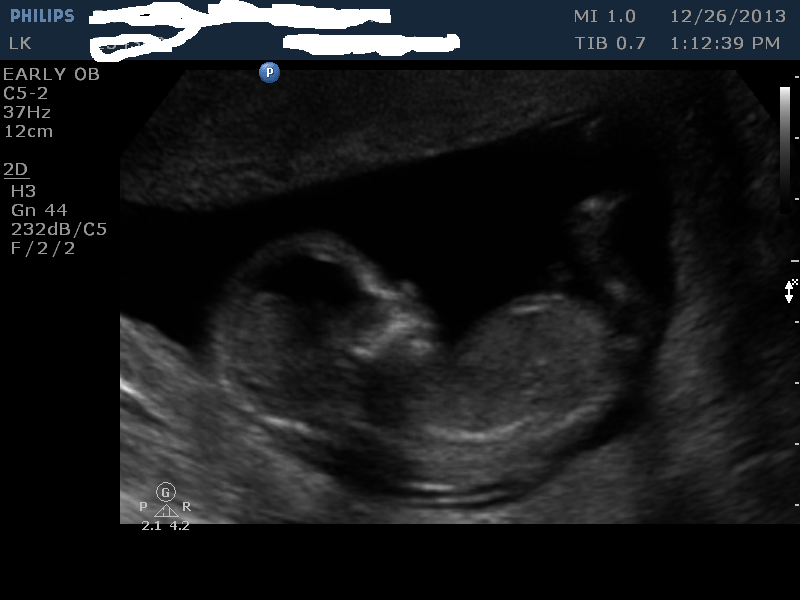

I had my 13 week scan done today. This is baby number 5, I currently have 4 girls and 1 boy. We would be happy either way. I just find it fun guessing. I do not think any of the pics have a good nub, but maybe I am wrong.

Nub guess?

skull guess?

placenta guess? (not sure it is even in photo)

Attachment 15894